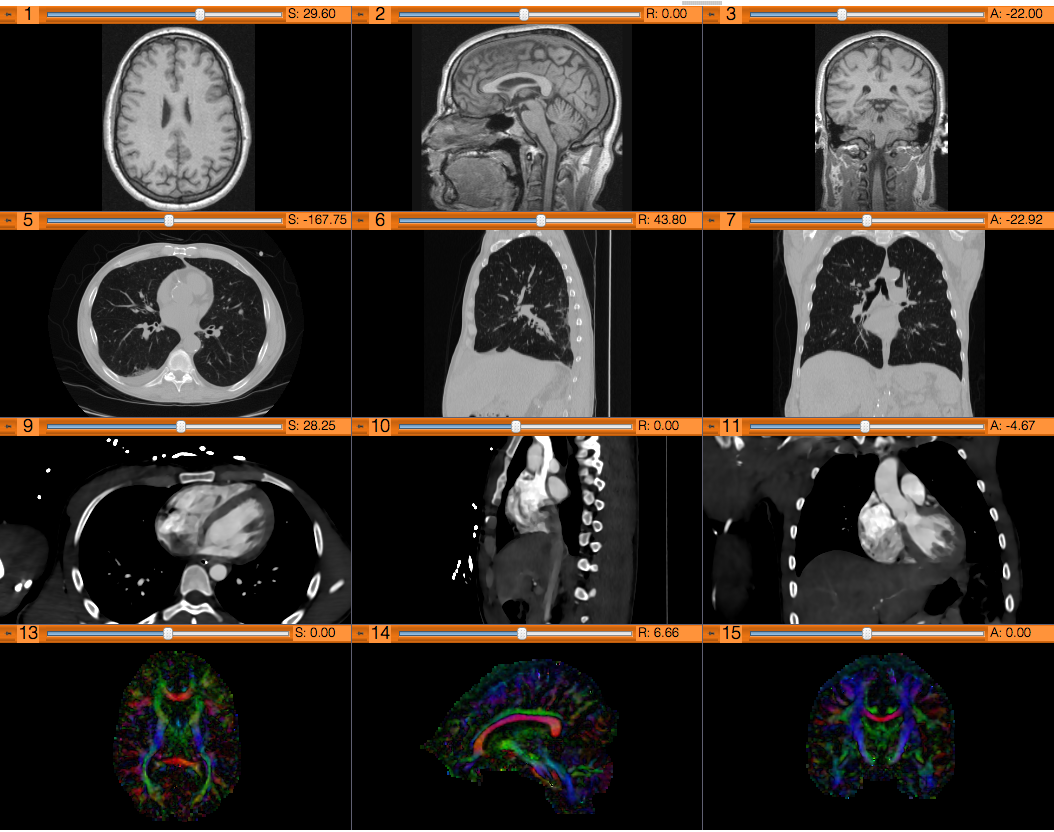

The Basics of Data Loading and Visualization tutorial shows how to load and visualize DICOM images and 3D models in 3D Slicer.

Introduction to the advanced 3D visualization capabilities of 3D Slicer.

The DICOM and Slicer tutorial provides an introduction to the DICOM standard and shows how to load and visualize DICOM datasets in 3D Slicer.

Guides through 3D data loading and visualization of DICOM images for Radiology Applications in 3D Slicer.